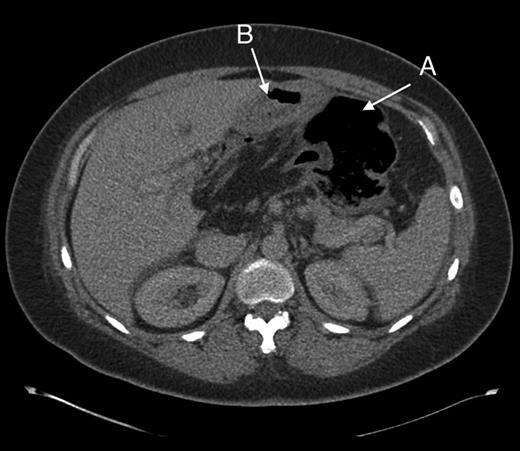

Computed tomography was used for diagnosis. Although initially reported as caecal volvulus, in hindsight there were features indicative of the herniation. (Figs 2 and 3).

Axial section through upper abdomen showing (A) distended caecum and (B) behind the stomach.

In retrospect there are several radiological features that could have clinched the diagnosis (see Figs 1–5), which have previously been described in the literature [6]. These include: (a) an absence of colon in the right gutter, (b) presence of mesentery between the portal vein and the inferior vena cava, (c) the presence of gas or fluid in the lesser sac, (d) the presence of terminal ileum and ascending colon displaced superiorly in the sub-hepatic space.